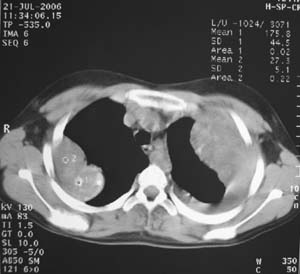

女性,17岁,一年前因股骨病变截肢,现胸憋。

左肺巨大肿块,内散在斑点状高密度骨化影,右肺见多发结节灶,双侧胸膜局限性增厚。有骨肉瘤病史,支持骨肉瘤手术后转移。